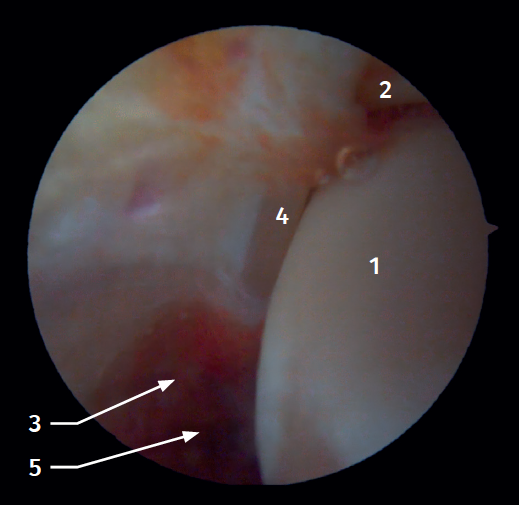

Visión artroscópica anterior

El 20% del LTPA es intraarticular(7). Cuando realizamos un acceso anteromedial del tobillo dirigiendo el artroscopio hacia lateral podemos ver las fibras distales del LTPA con su disposición oblicua y su continuación con el ligamento peroneo-astragalino anterior (Figura 2). Si avanzamos dentro de la articulación tibioastragalina, veremos la articulación tibioperonea distal con el receso sindesmal ocupado de tejido sinovial (Figura 3).

Figura 3. Visión artroscópica anterolateral de un tobillo derecho al introducirnos en la tibioastragalina. 1: cúpula astragalina; 2: cara articular de la tibia; 3: peroné; 4: articulación tibioperonea distal; 5: fibras distales del ligamento tibioperoneo anterior.